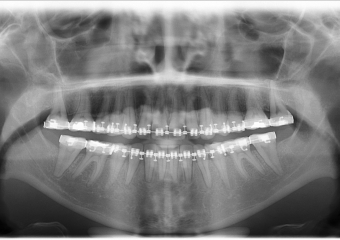

Raio x inicial

Raio x após a cirurgia realizada em 2015